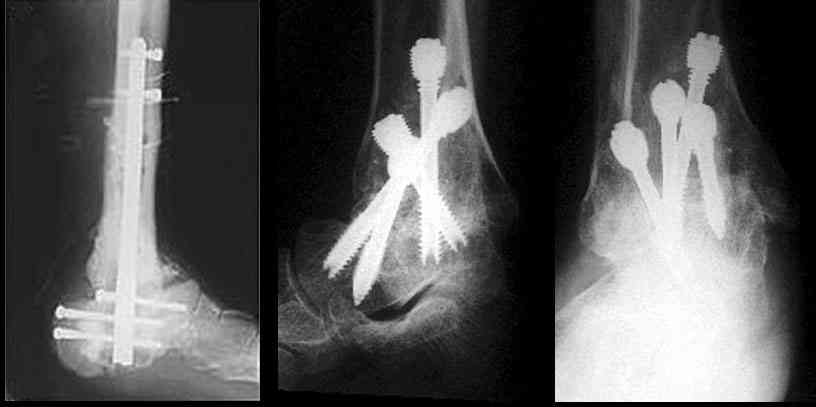

Можно: 65-летняя пациентка, оперирована по поводу несросшегося в гипсе перелома лодыжек с патологической вальгусной установкой стопы и выраженным нарушением опрной функции. Оперирована через 6 месяцев после травмы. Рентгенограммы через 4 месяца после операции.

С уважением, А.Семенистый.

Существуют специальные системы для артродеза голеностопного сустава. См. приложение

Уважаемый А.Семенистый. Складывается впечатление, что вы выполнили трехсуставный артродез, уж больно длинные блокирующие винты. Не мешают ли они пациентке при ходьбе?

Да конечно винты длинноваты! Мешают ли ходить? Во всяком случае субьективно пациентка удовлетворена. Ходит, естевственно, хуже чеи до травмы, но намного лучше, чем до операции.